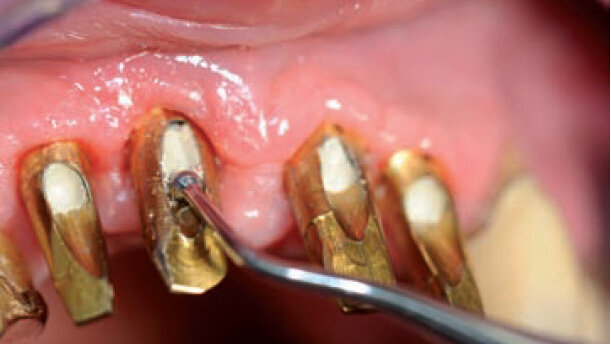

Dans le cas qui nous occupe, la réalisation du souhait du patient faisant suite au remplacement parfaitement réussi des dents, malgré la perte de l’os alvéolaire et l’état problématique de la gencive (Figs. 1 et 2), a été facilitée par une collaboration étroite avec la société Zahntechnik Zentrum Eisenach. Nous avons déjà décrit la procédure chirurgicale entreprise pour ce cas (Liebaug et Wu, 2011).5

Des implants OsseoSpeed™ TX Profile (DENTSPLY Implants), dont le col est biseauté et adapté à la forme anatomique de l’os, ont été utilisés pour les positions dentaires 11, 12, 21 et 22. Ces implants sont spécialement conçus pour préserver l’os mar - ginal dans une crête alvéolaire présentant une inclinaison anormale de la face tant vestibulaire que linguale, autrement dit, pour couvrir 360 degrés autour de l’implant.6 Des piliers ATLANTIS (DENTSPLY Implants), fabriqués sur mesure pour le patient, ont été prévus afin de réaliser la restauration prothétique finale la plus parfaite possible après, l’implantation et l’ostéointégration pleinement réussies. Comme décrit par Noelken (2011),7 l’os marginal peut être préservé à un coût relativement bas grâce à l’utilisation de ces implants nouvellement apparus, sur le marché dentaire. Un soutien optimal du tissu mou peut être obtenu au moyen des piliers individualisés.

En ce qui concerne ce patient de 67 ans, les implants ont été désenfouis après une phase de cicatrisation de quatre mois, en pratiquant une incision au milieu de la crête alvéolaire des positions dentaires 11, 12, 21 et 22 (Fig. 3).

La pose d’une restauration provisoire vissée après le prétraitement prothétique et le modelage du site implantaire, ou le recours à un appareil amovible temporaire, dépend considérablement des ressources financières du patient. Outre l’utilisation des coiffes de cicatrisation inhérentes au système, les restaurations provisoires facilitent le modelage, la préparation et la stabilisation du tissu mou péri-implantaire pendant et après la phase de cicatrisation. Comme la prothèse provisoire offre à la fois la fonctionnalité et l’esthétique qui satisfont le patient, un modelage supplémentaire du tissu mou a été réalisé au moyen de coiffes ou de piliers de cicatrisation particuliers (Figs. 4 et 5).

La connexion conique entre l’implant et le pilier simplifie également l’intégration de ce dernier (Fig. 6). Toutefois, en ce qui concerne les implants Osseo Speed™ TX Profile biseautés, une attention toute particulière doit être portée au transfert précis de la situation clinique au modèle, lequel est fabriqué au moyen d’auxiliaires de moulage et de piliers de transfert lors de la coulée de précision de l’empreinte. Cette phase du traitement requiert une expérience spécifique et un bon sens intuitif.